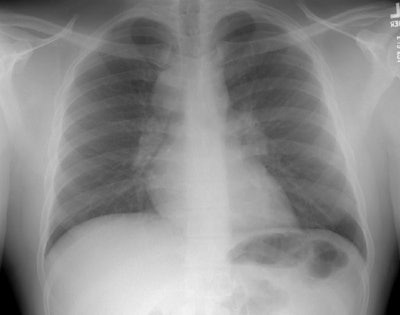

The chest radiograph below is from 1993. At that time this patient was diagnosed with sarcoid. His chest radiograph demonstrates the presence of bilateral hilar and right paratracheal adenopathy. The patient was lost to follow-up and presented in early 1996 due to complaints of increasing fatigue and shortness of breath. A follow-up chest radiograph was obtained.